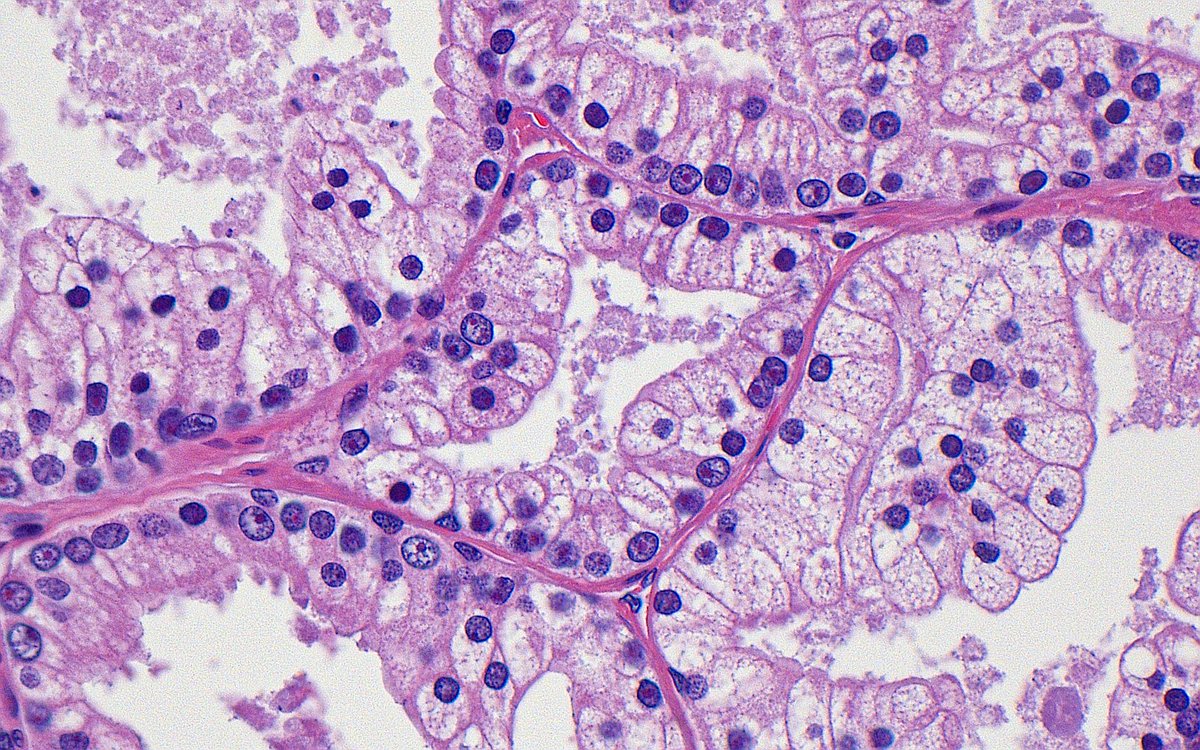

Prostate cancer...or...benign prostatic hyperplasia?

➡️Answer: Prostate cancer, pseudohyperplastic

(One clue: nucleoli in the high mag image!)

#GUpath #pathology #prostate #oncology #urology